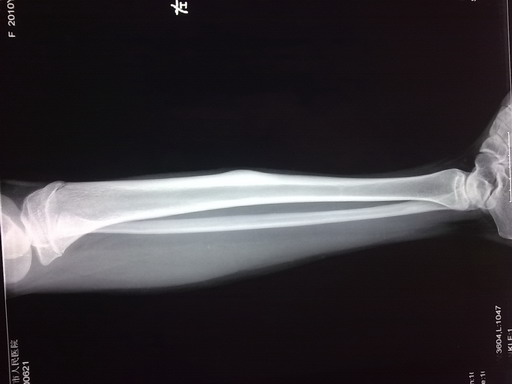

女孩,14岁,小腿疼痛一周,局部隆起,质硬,无红肿热痛

你侧胫骨中段见块状骨性突起。边缘清,并见硬化。考虑骨软骨瘤。

胫骨骨干皮质梭形增厚,虽无瘤巢,也考虑骨样骨瘤,原因不明,可能与感染有关,服用水杨酸制剂看看。

鉴别:骨化性纤维瘤、骨瘤、慢性骨膜下脓肿。

你侧胫骨中段见块状骨性突起。边缘清,考虑骨样骨瘤

左胫骨中段内前方骨皮质梭形增厚,髓腔未见累及,无骨膜反应。考虑良性病变。我考虑1低毒感染。

2骨样骨瘤:骨硬化较重,可能包埋了“瘤巢”。不象的地方就是病史不太支持:病程比较短,症状比较轻。试服用水杨酸制剂看看。

侧胫骨中段见块状骨性突起。边缘清,并见硬化。考虑骨软骨瘤。

考虑左胫骨中段骨样骨瘤。

左胫骨中段骨样骨瘤可能。隔期观察。

考虑 左胫骨中段骨样骨瘤。

考虑骨样骨瘤。病灶内部结构显示不清,请调调ct窗宽窗位。